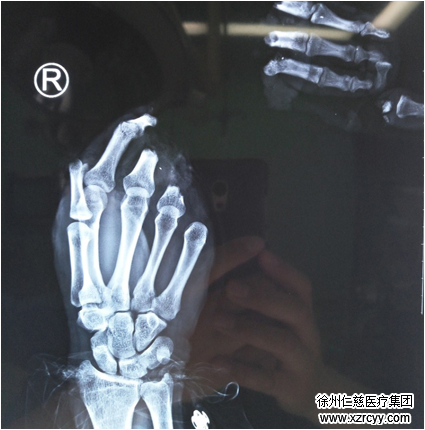

术前

术前检查

当日急诊值班的手外一病区李刚医生介绍,小鹏来院时已超过四个小时,右拇指及中环小指自近节离断,示指自中节完全离断,指体满布泥垢,离断指体挫伤严重,血管神经呈鼠尾状抽出,屈伸肌腱均自前臂长段抽出。如在6-8小时内无法恢复血运,指体坏死的风险将大大提高。